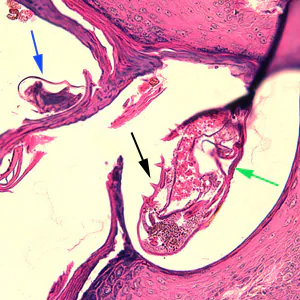

Sarcoptes scabiei mites in tissue specimens.